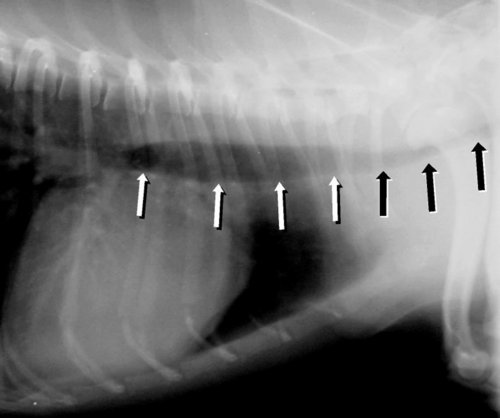

Bei bakteriellen Darmentzündungen ist der Kotabsatz bis zu sechsfach erhöht und flüssig bis blutig. Allgemeinstörungen, zum Teil schwerer Natur, wie allgemeine Schwäche, Verlust von Körperflüssigkeiten wir Wasser oder sogar Blut sind die Folge. Es können aber auch die Symptome der Primärerkrankung, viral oder parasitär, im Vordergrund stehen, wenn es sich bei den Bakterien nur um sekundäre Krankheitserreger handelt. Bei der klinischen Untersuchung fallen neben einem schlechten Kreislaufzustand auch im Bereich des Bauchraums stark erweiterte und aufgegaste Darmschlingen auf, die auch bei bildgebender Diagnostik -wie dem Röntgen- ins Auge fallen.